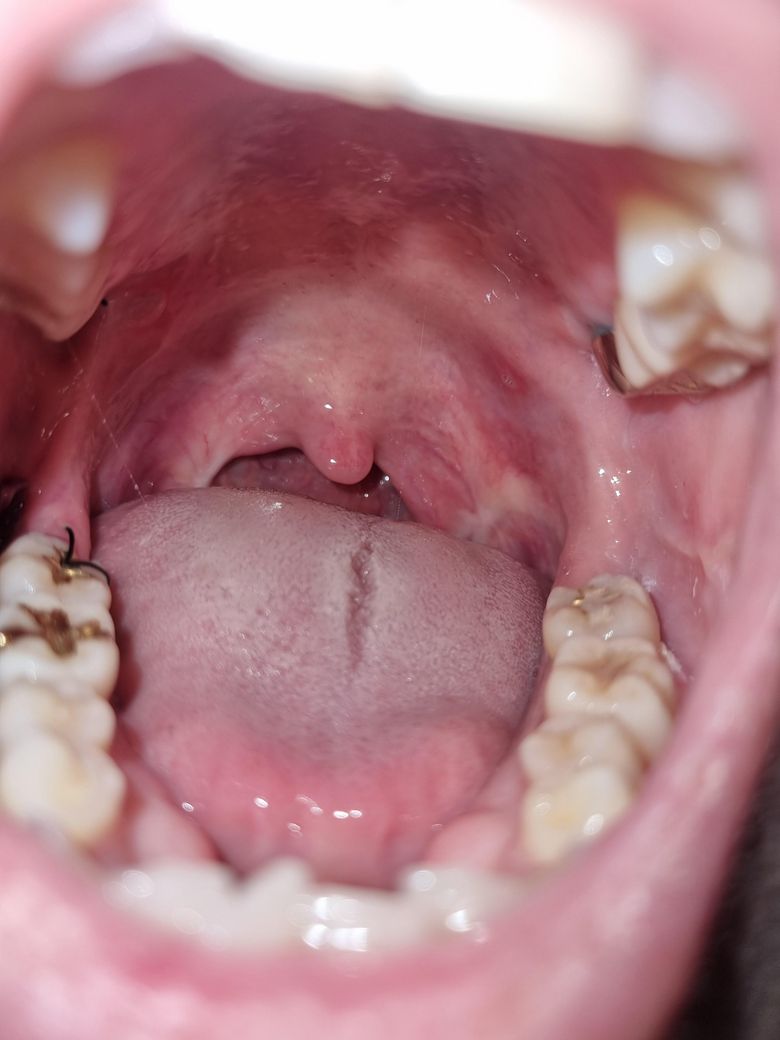

몇일전부터 입천장에구내염이생겼고 입이건조하고 텁텁하네요 . 사진상으로봤을때 칸디다증인가요?

• 1번 째 사진

사진으로는 정확한 진단 불가능하며 병원 방문하셔서 직접 육안으로 진료 보셔야 합니다

칸디다증을 의심할 정도는 아닌 듯 한데 정확한건 진료 봐 보셔야 해요

사랑니를 뽑고 항생제를 사용한 후 구내염과 입 건조, 텁텁한 느낌이 발생하는 것은 칸디다증을 포함한 여러 원인으로 발생할 수 있습니다. 항생제를 많이 사용하면 장내 유익균이 줄어들어 곰팡이균인 칸디다균이 과다 증식할 수 있고, 이로 인해 입안에 하얗고 부드러운 병변이 생길 수는 있죠. 칸디다증은 일반적으로 입안의 하얀 점막 위에 표면적으로 나타나는 경우가 많지만, 구내염과 입 건조는 칸디다 외에도 다른 원인으로 발생할 수 있습니다.

우선 구강 위생을 관리하고 수분을 자주 섭취하는 것이 중요합니다. 만약 증상이 지속되거나 칸디다증을 의심할 수 있는 하얀 병변이 계속된다면 이비인후과나 구강내과를 방문하여 정확한 진단과 치료를 받는 것이 좋습니다.